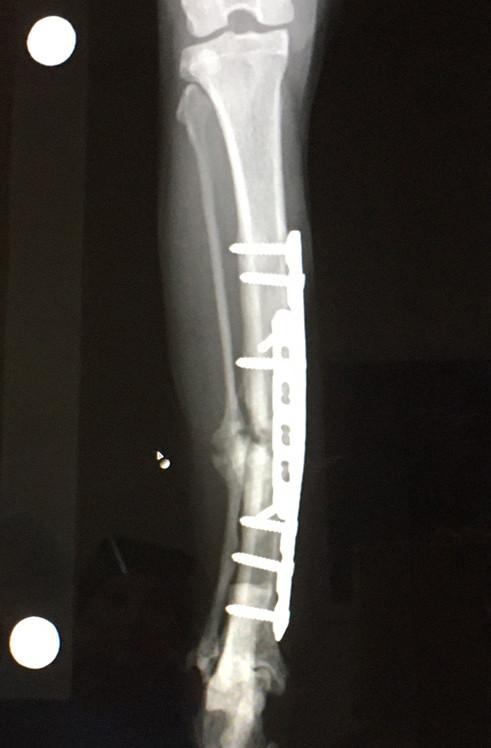

骨折猫手術から2ヶ月経過しました。

前回の6週間検診で問題ない範囲だけどプレートがちょっと曲がってる発覚して

2ヶ月くらい経ったよ検診に行ってきました。

骨形成はぼちぼち進んでました。

目に見えてはっきりなんか出来てるのがわかります。

でもまだまだケージで安静にしてくださいだそうで。